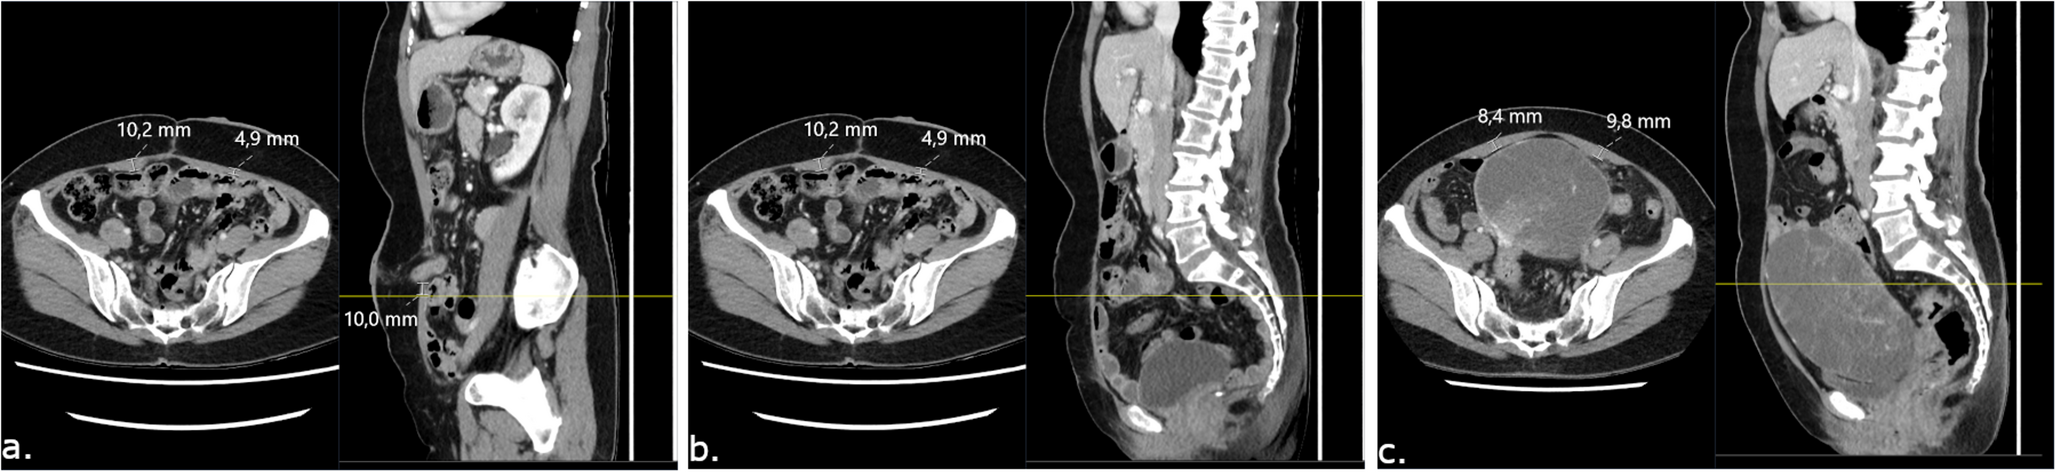

First, postoperative images with the stoma in situ were reviewed to establish the cranio-caudal location of the stoma within the ARM, using the spinal vertebrae as reference. The presence of PSH was evaluated, defining PSH as any herniation of intra-abdominal contents ventral to the anterior rectus sheath. Stoma prolapse as well as the inevitable presence of stoma intestinal mesentery was not considered a PSH. On axial slices, anteroposterior (AP) thickness of the ARM was measured using a picture archive and communications system (PACS) [SECTRA, Linköping, Sweden]. The AP thickness of the ARM (ARM-AP) was defined as the muscle including the rectus sheath. Measurements were made on axial slices one centimetre caudal to the caudal-most aspect of the stoma orifice, at the latero-lateral point where the ARM was thickest. The rationale behind measuring one centimetre caudal to the stoma orifice was that neuroanatomically, atrophy of the ARM should occur at the level of neurovascular compromise and caudal to that. Furthermore, the region immediately adjacent to the stoma orifice would be affected by fibrosis and some degree of distortion, making measurements difficult to interpret. The same ARM measurements were made on preoperative scans. To ensure that measurements were made at the same cranio-caudal and latero-lateral levels as with postoperative images, the vertebral column and surrounding structures were used as references to identify the corresponding axial slices. Measurements of the contralateral ARM were made at the same cranio-caudal level, measuring the AP thickness at the thickest portion of the muscle at this level. The ARM measurement procedure is illustrated in Fig. 1. Differences between preoperative and postoperative ARM-AP (ΔARM-AP [mm]) measurements were calculated bilaterally in all cases.

Fig. 1

Abdominal rectus muscle (ARM) measurements on computerised tomography (CT) scans of rectal cancer patients subjected to tumour resection with permanent end colostomy. First, on postoperative CT (a.), the location of the stoma is identified, and ARM measurements are made on axial slices 1 cm caudal to the stoma aperture. On sagittal slices (b.) the craniocaudal level at which the measurements were made is then established in relation to fix structures such as the vertebral column. Then, on preoperative imaging (c.) the same craniocaudal level is identified and ARM measurements are made on axial slices the same way as in (a.)